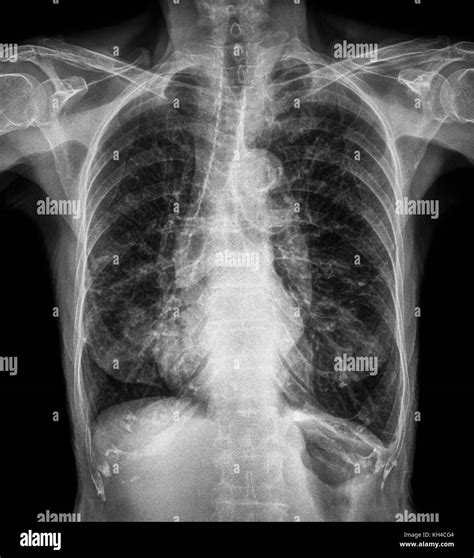

A bronchitis X ray is a crucial diagnostic tool that helps healthcare providers visualize the lungs and bronchial tubes. This imaging technique uses X-rays to create detailed images of the chest, allowing doctors to identify any abnormalities or inflammation. The bronchitis X ray can reveal:

• Inflammation and swelling of the bronchial tubes

• Presence of mucus or fluid in the lungs

• Signs of infection or pneumonia

• Structural abnormalities in the lungs

Interpreting Bronchitis X Ray Results

Interpreting the results of a bronchitis X ray requires the expertise of a radiologist or healthcare provider. The images are carefully examined for signs of inflammation, infection, or other abnormalities. Key findings that may be noted include:

• Increased density or opacity in the lungs, indicating inflammation or fluid buildup

• Thickening of the bronchial walls

• Presence of nodules or masses

• Signs of pneumonia or other respiratory infections